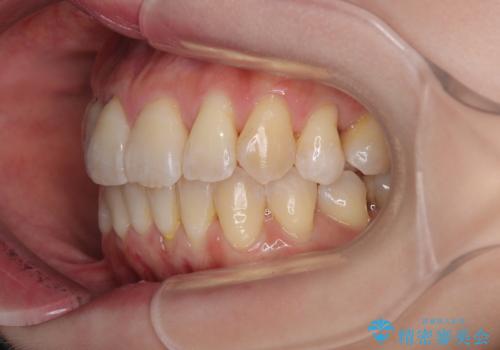

- 上下前歯のデコボコを気にして来院された患者様です。

デコボコは顕著であるものの、口元の突出感は強くないため、非抜歯にて矯正治療を行うこととしました。

元々の叢生と歯肉退縮傾向になる歯肉であったため、ブラックトライアングルが目立つことが想定されました。

治療過程でブラックトライアングル改善のため、IPR(歯と歯の間を削る)を活用しました。